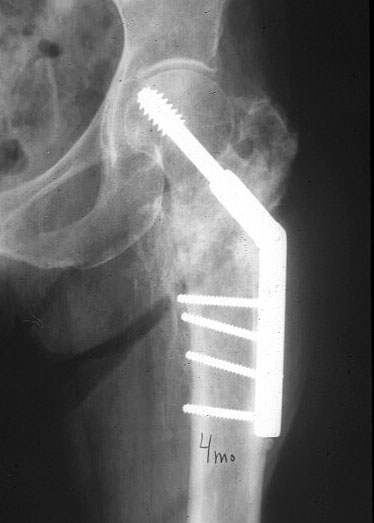

Это 4-фрагментный перелом, традиционно-современная фиксация - это динамический бедренный винт, DHS. Либо какой-либо из проксимальных бедренных гвоздей, предназначенных для ранней полной нагрузки, из-за меньшего доступа, других преимуществ перед DHS нет. Если доступен только реконструкционный гвоздь, то винты вводить надо очень точно и аккуратно субхондрально, т.е. максимальной длины, а то прорежутся в головке.

Вот пример наших американских коллег про DHS. Видно, как стелескопировались отломки, хотя поначалу был оставлен диастаз.